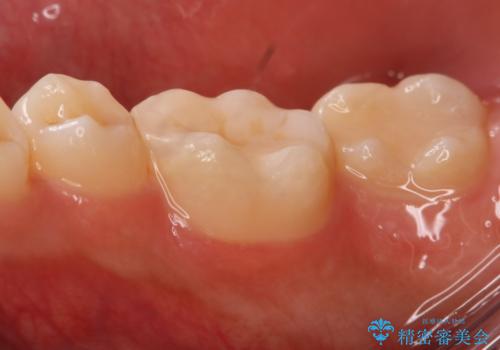

上はう蝕が歯頚部まで達していたのでクラウンでの治療を選択しました。

銀歯直下もう蝕が進行していたので全て除去した上でCRにて裏層しています。